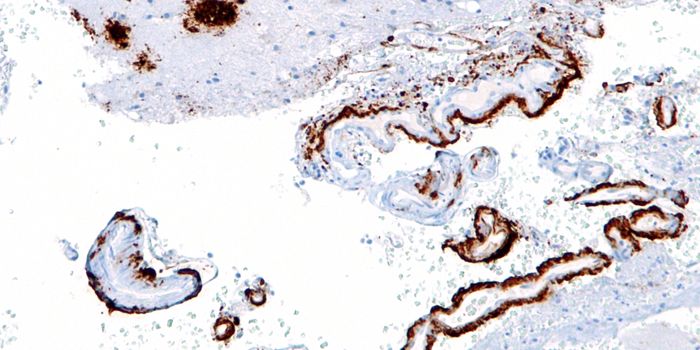

AUG 31, 2021Clinical & Molecular DXCellular stains are organic fluorescent dyes or fluorescent conjugates designed to localize to a specific organelle or c ...

SEP 07, 2016CancerWhen treating cancer, doctors have turned to immunotherapy to help target actual tumors instead of attacking all rapidly ...

![Anti-PRAME antibody [EPR20330]](https://d3bkbkx82g74b8.cloudfront.net/eyJidWNrZXQiOiJsYWJyb290cy1pbWFnZXMiLCJrZXkiOiJjb21wYW55X3Byb2R1Y3RfcHJvZmlsZV9pbWFnZV9mMzEwNTY4MGY1NmVmZjU3ZjZhMWRkZTU2M2Q4YjBmODZjMDJkNDE4XzMwMDA3MTg1ODEyLmpwZyIsImVkaXRzIjp7InRvRm9ybWF0IjoianBnIiwicmVzaXplIjp7IndpZHRoIjozMDAsImhlaWdodCI6MzAwLCJmaXQiOiJjb3ZlciIsInBvc2l0aW9uIjoiY2VudGVyIiwiYmFja2dyb3VuZCI6IiNmZmYifSwiZmxhdHRlbiI6eyJiYWNrZ3JvdW5kIjoiI2ZmZiJ9fX0=)